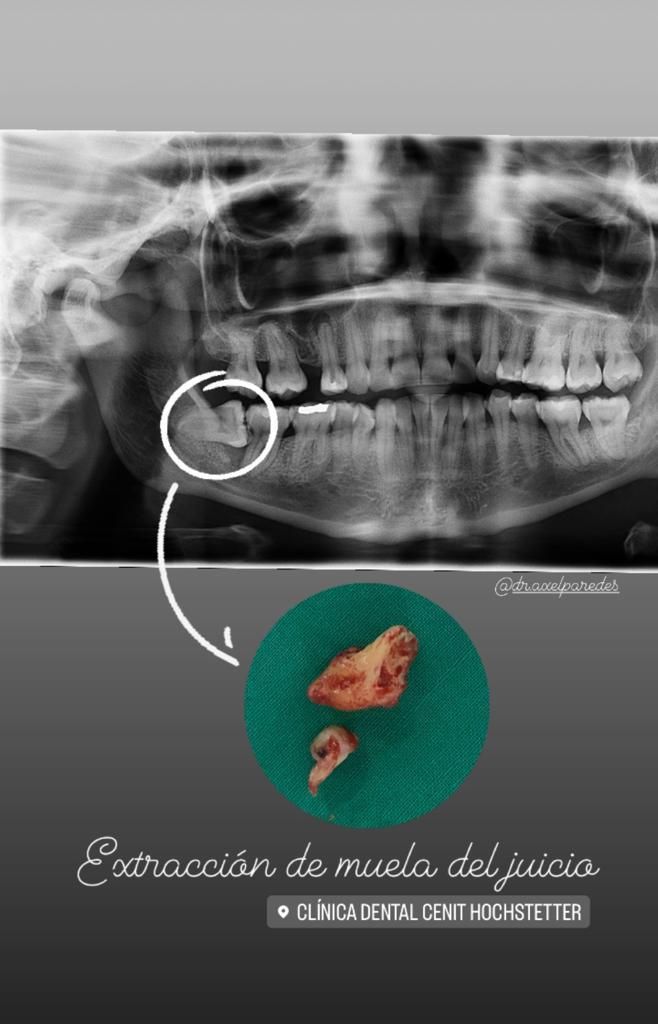

Diseño de Sonrisa con Implantes y Rehabilitación Oral

Descripción del caso:

Paciente tratado con cirugía de implante dental, finalizado con rehabilitación oral completa mediante coronas cerámicas y carillas estéticas, logrando un cambio integral en función y estética.

Procedimiento realizado en su totalidad por el Dr. Axel Paredes.

Antes y Después (imagen adjunta)

Temuco – Hochstetter 560, oficina 311